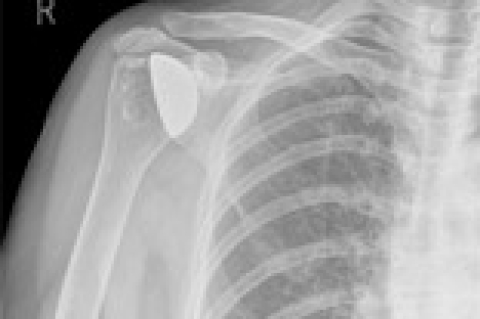

Things to Know before Shoulder Replacement Surgery

More than 53,000 shoulder replacements are performed in the US every year. Although not as common as knee or hip replacement, shoulder replacement surgery has become increasingly popular due to advances in implant material and design as well as minimally invasive surgical techniques that offer improved quality of life for people with significantly damaged shoulders.